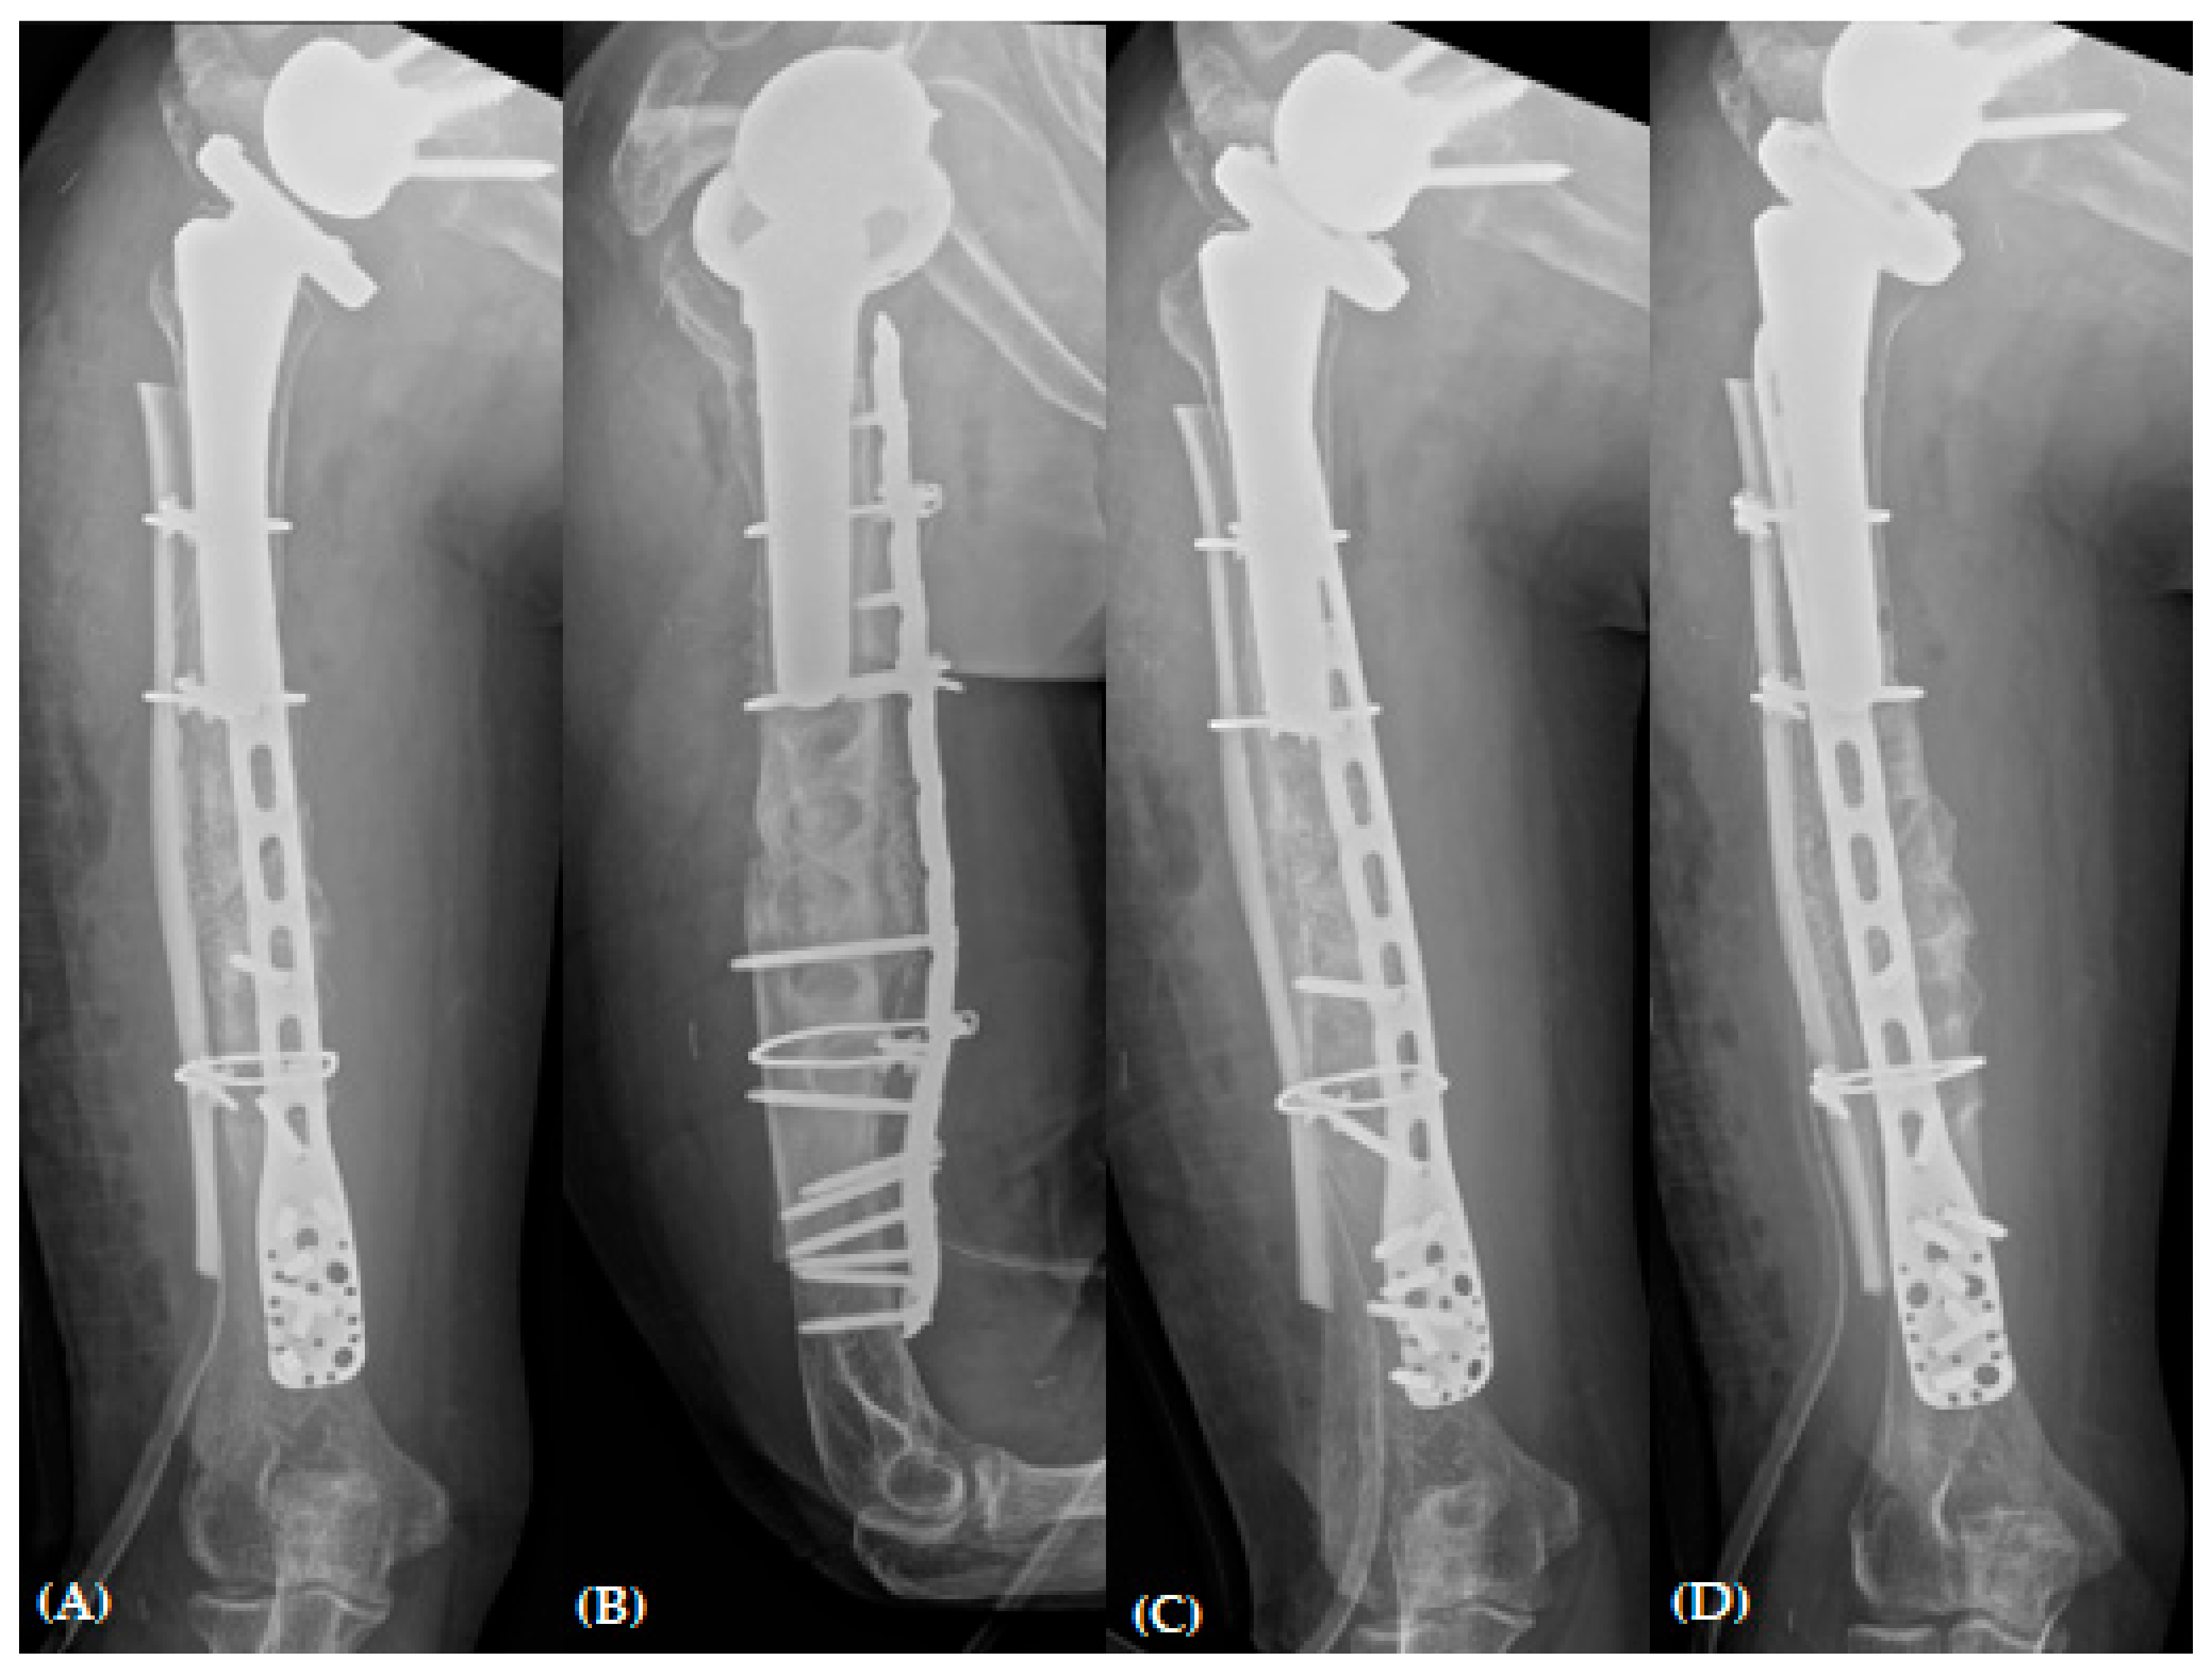

Figure 4. Plain radiographs of humerus (A) AP; (B) lateral and (C,D) oblique views 6 months after open reduction and plate osteosynthesis for periprosthetic fracture.

Upon reviewing the simple radiographs captured 3 months after the operation, we observed breakage of the proximal wires; all screws had loosened without pulling out, callus formation was absent, and varus deformity was noticeable (Figure 3). The patient was treated conservatively with an abduction brace for 6 months post-operatively. On simple radiographs captured 6 months post-operatively, the fracture site displayed bone absorption and a noticeable progression of varus angulation (Figure 4). Radiographic findings confirmed atrophic non-union, necessitating a comprehensive approach to address both stability and maintain the structure of the anatomical biology through revision osteosynthesis. In order to discern the weakness reported by the patient, a cervical spine evaluation, electromyography (EMG), and nerve conduction velocity study (NCV) were conducted, and all results were confirmed to be within normal range.